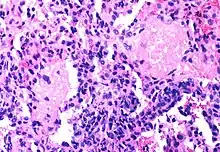

Pneumocystis jiroveci pneumonia

Mycobacterium avium complex

The diseases associated with AIDS, such as Pneumocystis jiroveci pneumonia (PCP) and Mycobacterium avium complex (MAC), are not caused by HIV, but rather result from the immunosuppression caused by HIV disease. As the immune system of an HIV-infected individual weakens, he or she becomes susceptible to the particular viral, fungal, and bacterial infections common in the community. For example, HIV-infected people in the Midwestern United States are much more likely than people in New York City to develop histoplasmosis, which is caused by a fungus. A person in Africa is exposed to pathogens different from individuals in an American city. Children may be exposed to different infectious agents compared to adults.[89]

HIV is the underlying cause of the condition named AIDS, but the additional conditions that may affect an AIDS patient are dependent upon the endemic pathogens to which the patient may be exposed.